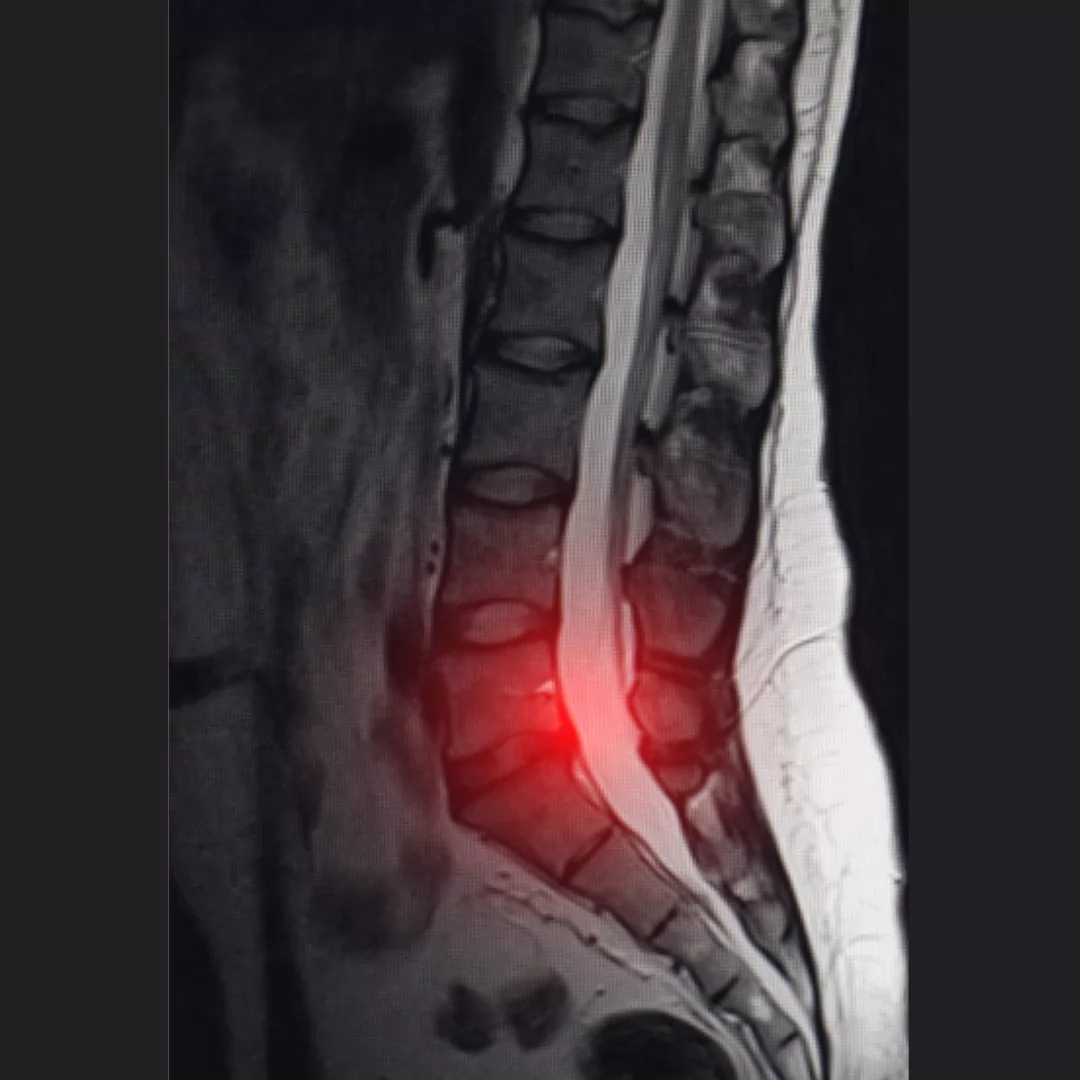

Lumbar Herniated disc; It is a disease that occurs as a result of herniation of these discs, which act as shock absorbers. There is a soft part called the nucleus pulposus inside the discs. There is a harder fibrous layer called the annulus fibrosus on the outside of this section. First, the anatomical integrity of the outer part is disrupted. And so the soft part inside is moved outward. The result of this situation is called herniation.

Herniated disc; compresses the spinal canal and the nerves passing through it. That, some chemicals released from the disc to the environment also affect the nerve roots then cause pain.

Physical examination and imaging methods (MR and X-ray) are evaluated together. Examination findings are the main guide in the diagnosis. MRI and X-ray findings are important to confirm the examination.